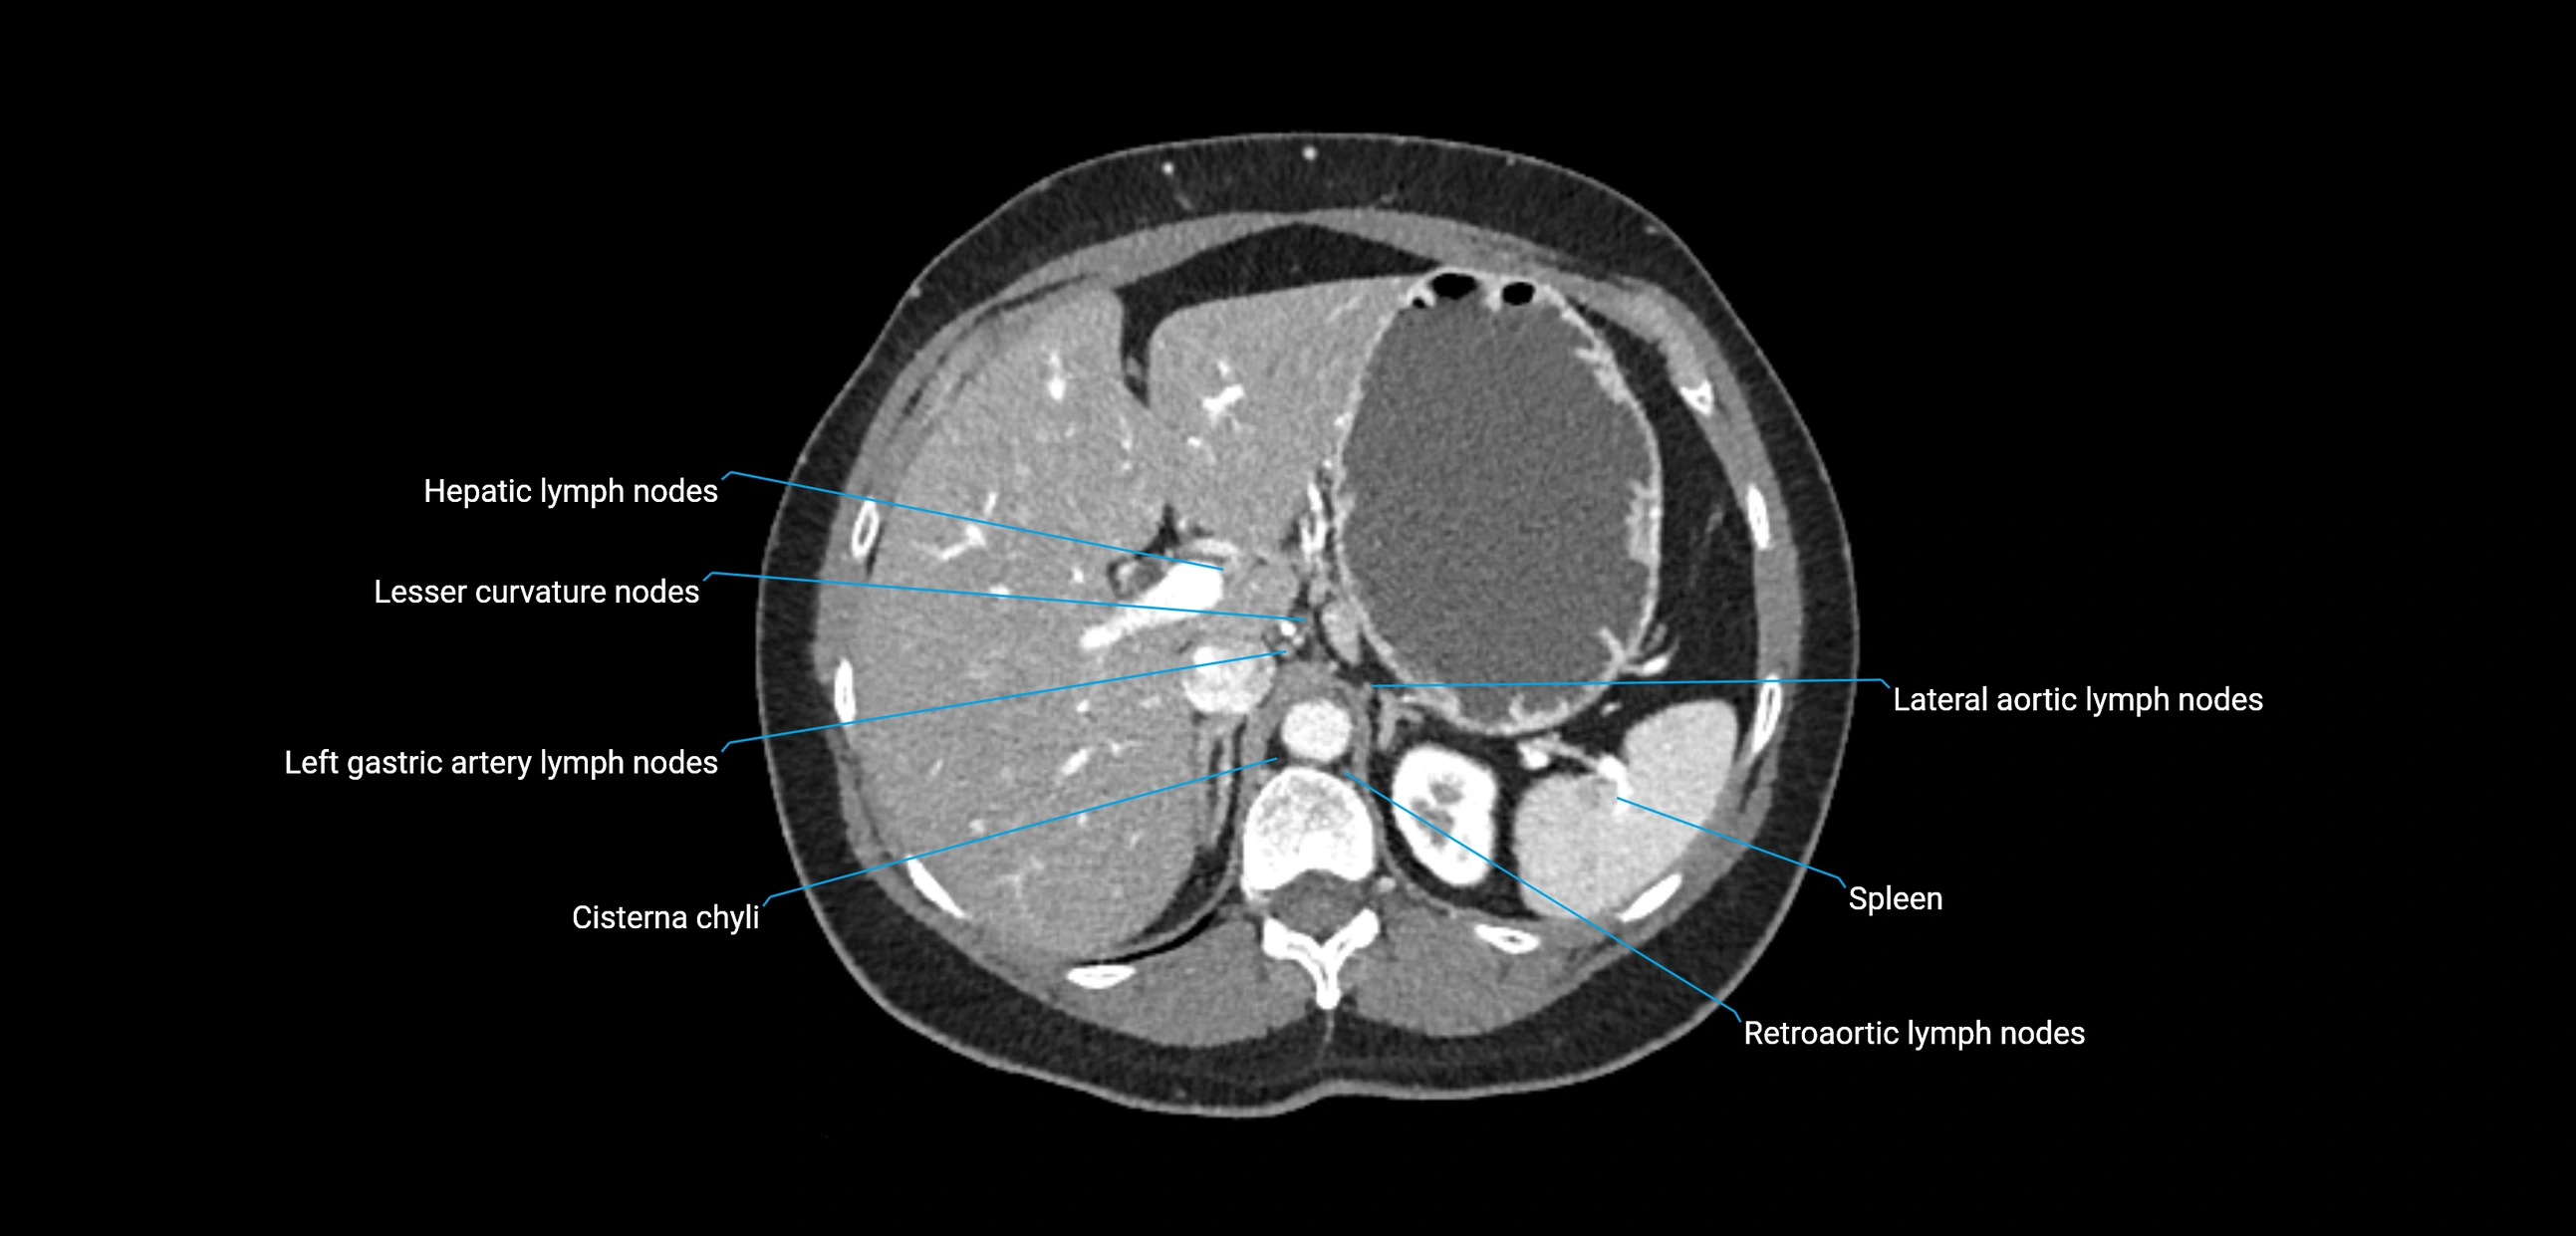

CT Appearance

CT Pre-Contrast:

• Nodes appear as soft-tissue density nodules adjacent to the aorta and IVC

• Calcification may be seen in chronic infections (e.g., tuberculosis)

CT Post-Contrast:

• Normal nodes enhance homogeneously

• Malignant nodes may show heterogeneous enhancement, central necrosis, or conglomerate formation

• Size >1 cm short axis is suspicious, though morphology and distribution are equally important

The lateral aortic lymph nodes (also called para-aortic lymph nodes) are a major group of retroperitoneal lymph nodes located along the abdominal aorta and its branches. They lie between the diaphragmatic crura superiorly and the bifurcation of the aorta at L4 inferiorly.

These nodes receive lymph from a wide range of abdominal and pelvic structures. Specifically, they drain lymph from the kidneys, suprarenal glands, gonads (testes/ovaries), uterus, uterine tubes, and pelvic organs, before converging into the lumbar lymphatic trunks, which terminate in the cisterna chyli → thoracic duct.